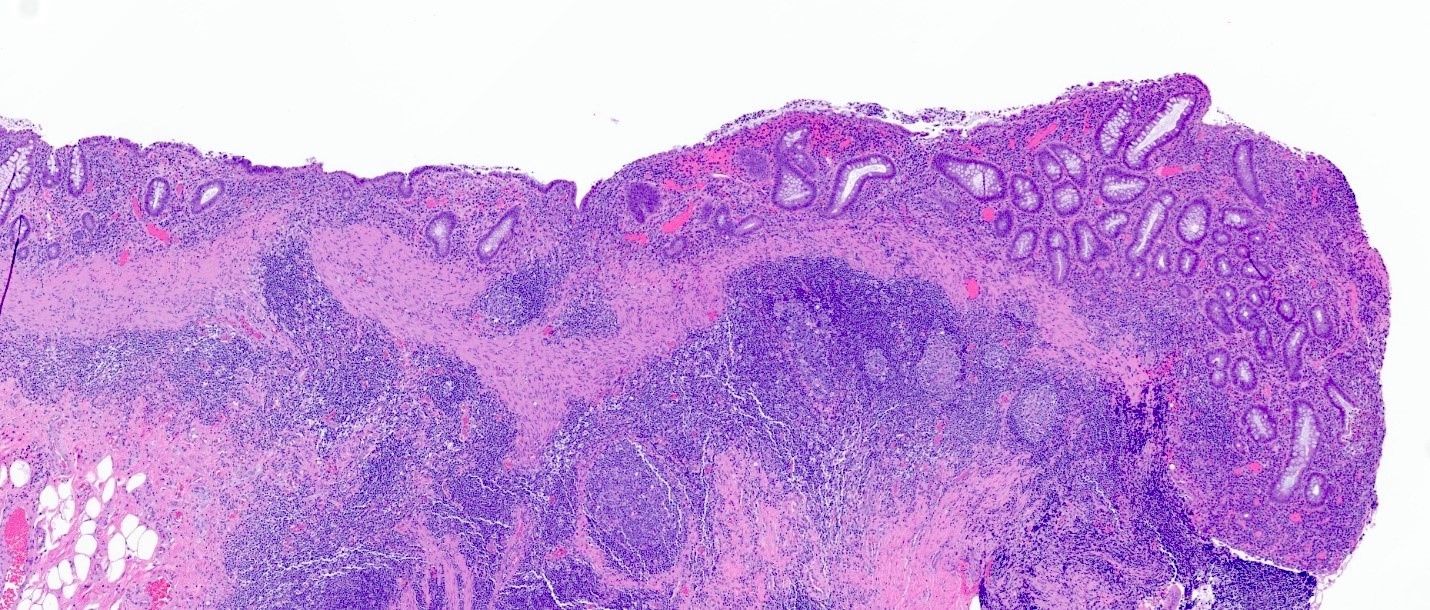

Microscopic (histologic) images

Contributed by Catherine E. Hagen, M.D. and Dustin W. Parsons, M.D.

Lymphoid aggregate and architectural changes

Ulceration

Microscopic (histologic) description

• Lymphoid follicular hyperplasia with germinal centers

• Muscularis mucosa hypertrophy, which is often patchy

• Architectural changes with distortion of crypts, crypt branching and loss of crypts

• Degenerative mucosal surface epithelium with cell exfoliation and pyknotic nuclei

• Loss of goblet cells and mucin

• Mucosal ulceration with granulation tissue

• Varying degrees of inflammation, with features of both activity (neutrophil predominant) and chronicity (lymphoplasmacytic)

• Focal edema

• Pseudopolyps

• Paneth cell metaplasia

• References: Hum Pathol 2022;123:31, World J Gastroenterol 2018;24:1734, Histopathology 1991;19:55

A 72 year old man with a history of colon cancer undergoes radiation therapy, followed by partial colon resection with construction of an ileostomy. He denies any history of inflammatory bowel disease. The image shown above demonstrates histologic findings of the resected portion of the colon. These findings are most consistent with which clinical presentation?

A. Diversion colitis. The construction of an ileostomy should always raise suspicion for the possibility of diversion colitis. The prominent lymphoid aggregates are likely the most characteristic finding associated with diversion colitis. Other features appreciated here include patchy hypertrophy of muscularis mucosa, ulceration and loss of colonic crypts. Answer B is incorrect because the clinical vignette does not suggest any fevers or bowel symptoms consistent with an infectious etiology. Infectious colitis typically shows a histologic pattern of acute self limited colitis without architectural distortion. Answer C is incorrect because the presence of lymphoid aggregates should favor diversion colitis over radiation colitis. Radiation colitis is typically pauci-inflammatory with evidence of lamina propria fibrosis and hyalinized ectatic vessels. Answer D is incorrect because while diversion colitis can have overlapping histologic features with inflammatory bowel disease, given that the patient denies any history of underlying inflammatory bowel disease, this is unlikely to be a manifestation of ulcerative colitis.